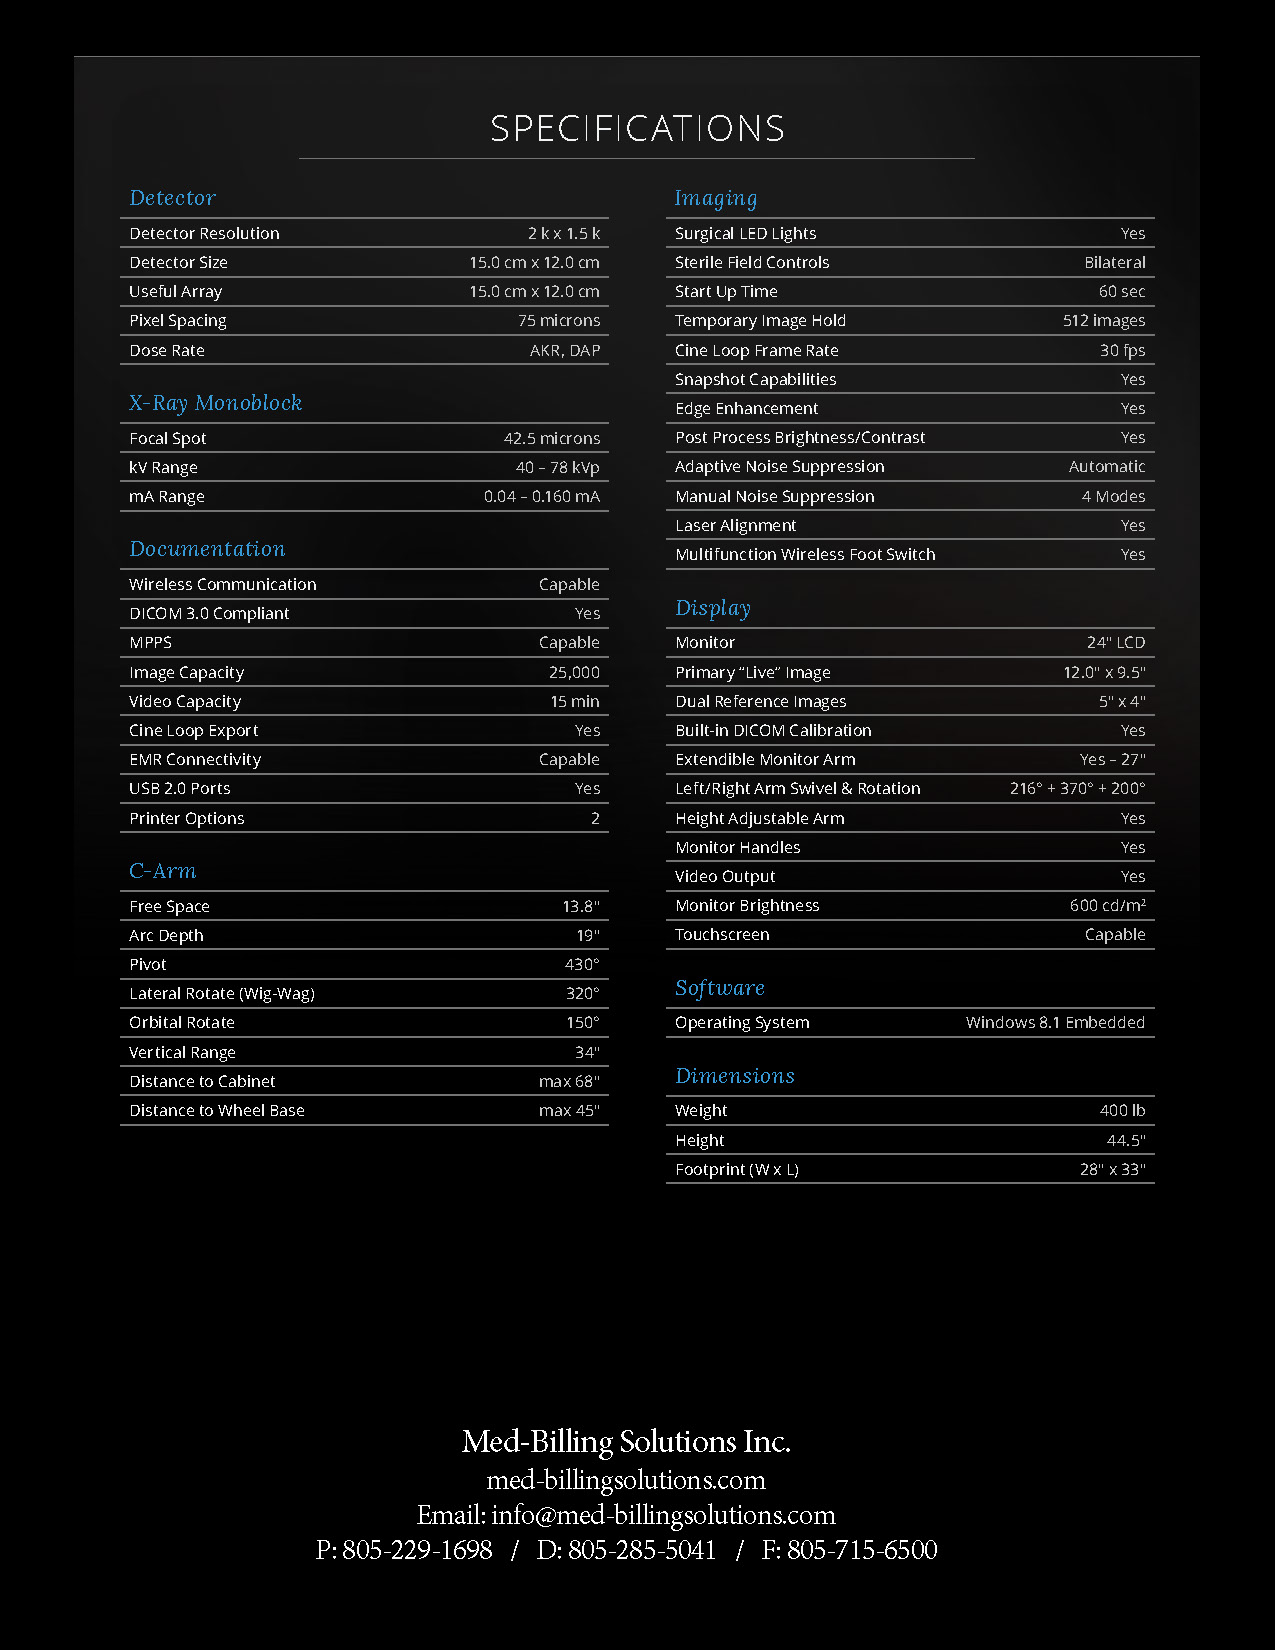

The Advanced Arthritis Relief Program (AARP) is a knee osteoarthritis (OA) treatment system that consists of fluoroscopic guided injections of Hyaluronic Acid, targeted Physical Therapy, and a special uploading Knee Brace. It’s MD, MP, and PA approved and covered by all major insurance carriers as well as Medicare.

2019 Fee Schedule & Coding Determination changes Osteoarthritis Joint Treatment & Pain Relief. After Standard of care for knee OA, MEDICARE requires patients try and fail viscosupplementation therapy prior to approving total knee arthroplasty (TKA). The AARP is this type of therapy that is approved by Medicare. It combines viscosupplementation with physical therapy and a specialized knee bracing procedure that has been delivering near perfect results.

2019 Fee Schedule & Coding Determination changes Osteoarthritis Joint Treatment & Pain Relief. After Standard of care for knee OA, MEDICARE requires patients try and fail viscosupplementation therapy prior to approving total knee arthroplasty (TKA). The AARP is this type of therapy that is approved by Medicare. It combines viscosupplementation with physical therapy and a specialized knee bracing procedure that has been delivering near perfect results.